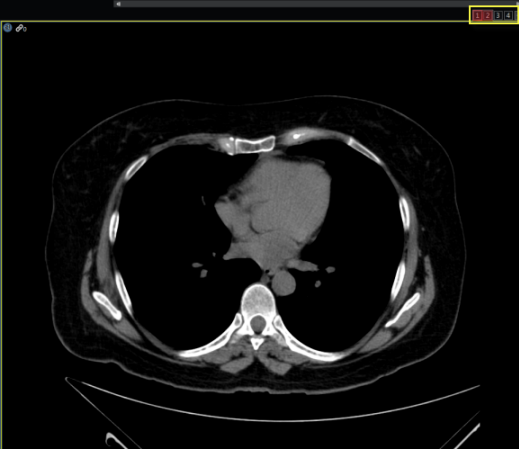

When Layout Edit Mode is activated, a grids matrix will be located in the center of the image frame to customize another layout.